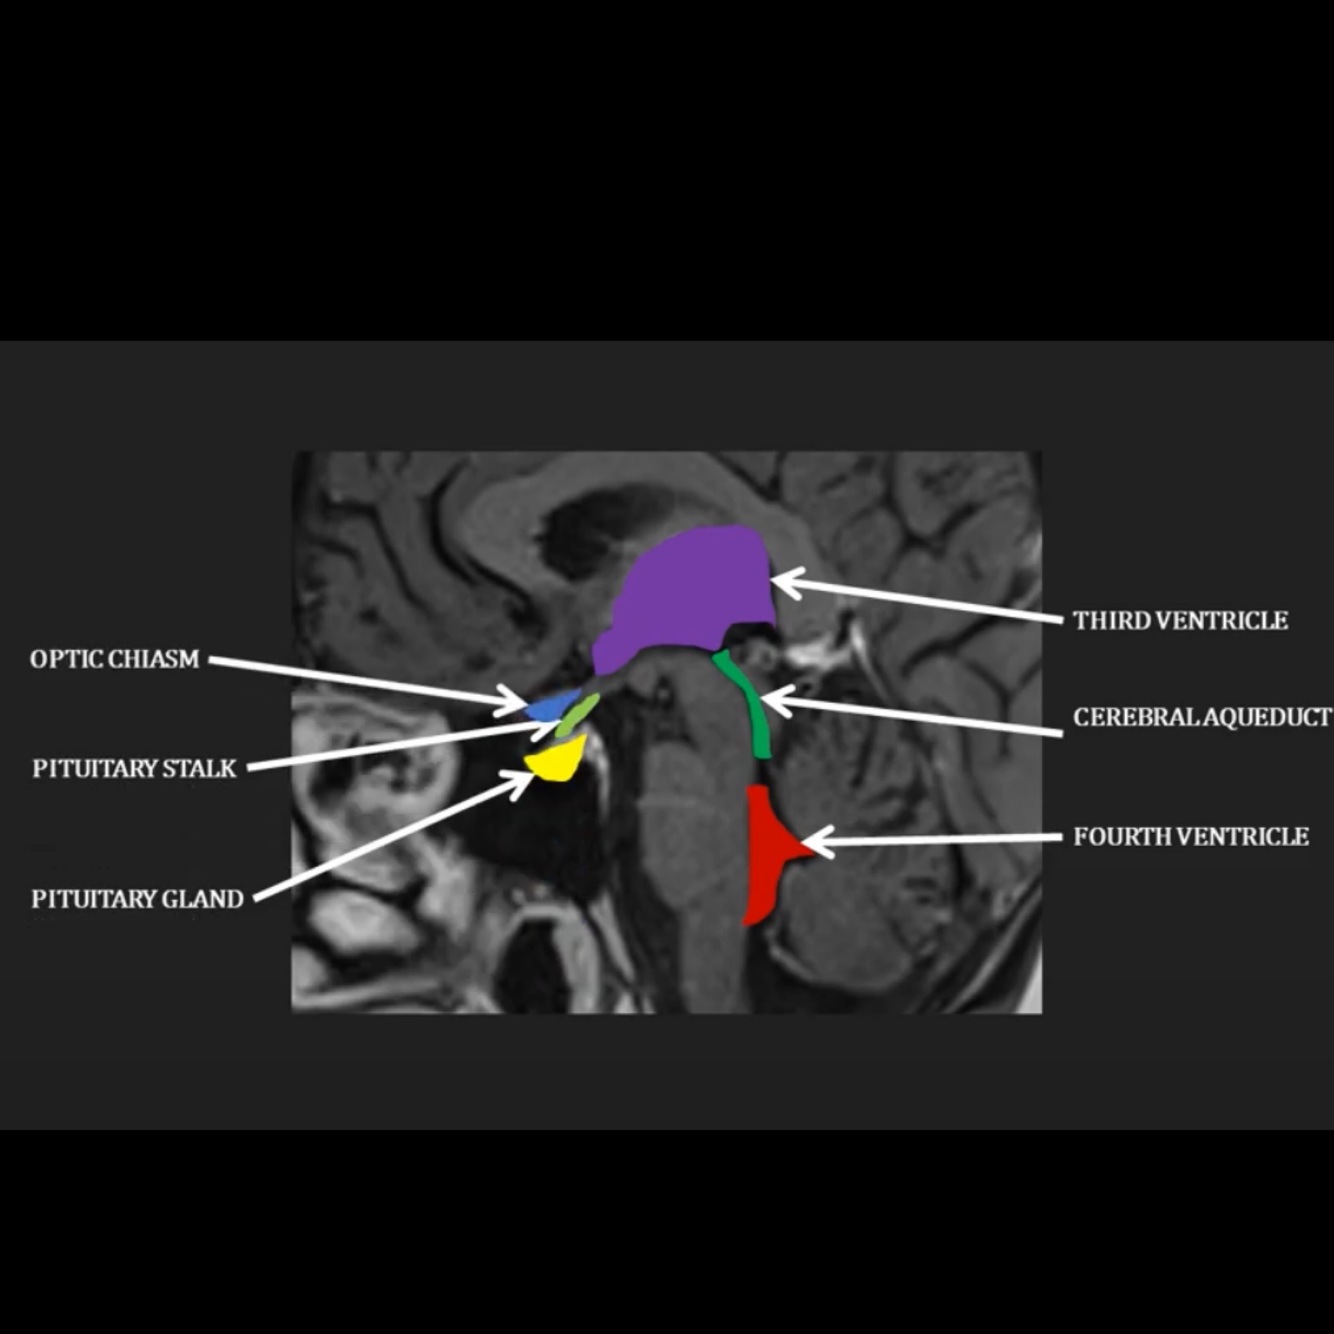

Where does the CSF flow through the brain as visible on this diagram?

Through the third ventricle into the cerebral aqueduct, into the fourth ventricle

Where does the pituitary gland sit in relation to the ventricles?

Where is the pituitary stalk?

Anteriorly in the pituitary fossa

Pituitary stalk superior to pituitary gland

Where does the optic chiasm sit in relation to the pituitary gland?

Immediately superior to pituitary stalk